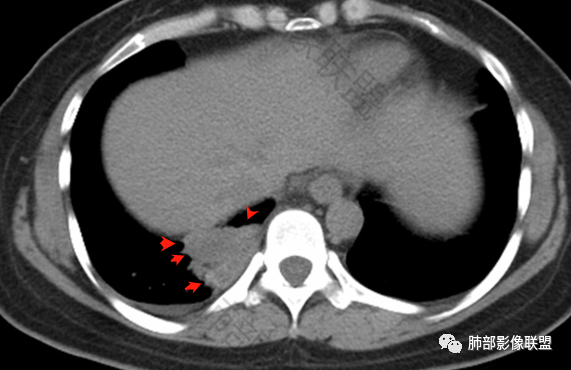

2.右肺下叶脊柱旁类椭圆形块影,边界清楚,密度偏低,隐约见轻度强化囊壁样结构,均匀一致,中央区域未见强化,因属囊样块影。前外缘处显示“壁外”小范围轻度强化软组织密度影,未见磨玻璃晕。

3.块影边缘见匍行血管影,未显示体循环供血。病灶与支气管关系未能显示或呈现。

病灶相邻胸膜轻度强化,未见壁层胸膜侵入或突破。

5.右侧胸腔少量积液。